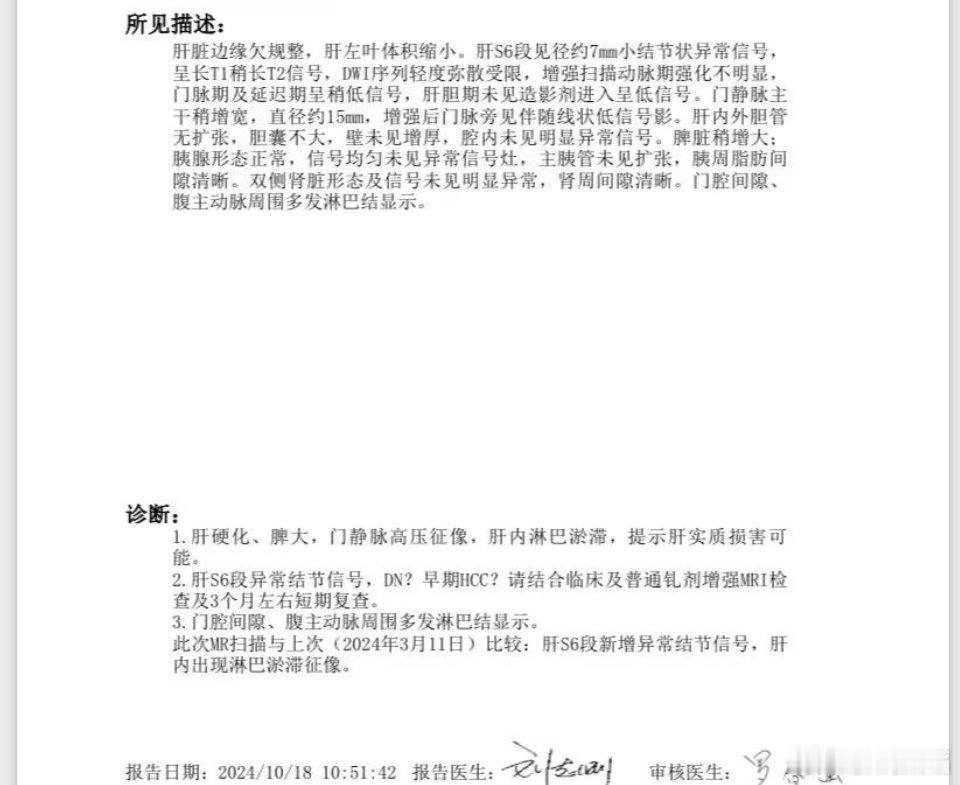

他们建议是说,因为甲胎和凝血也高了,现在这个位置还比较深,在那个切除面儿比较大。他建议就不管性质,直接进行消融,处理了就安心。为后面如果病情发展留一些空间

1\消融的主要问题是,不能确定病变性质

2\当然,如果的确外科切除位置不好弄,也只有这个方案。

他们建议是说,因为甲胎和凝血也高了,现在这个位置还比较深,在那个切除面儿比较大。他建议就不管性质,直接进行消融,处理了就安心。为后面如果病情发展留一些空间

1\消融的主要问题是,不能确定病变性质

2\当然,如果的确外科切除位置不好弄,也只有这个方案。